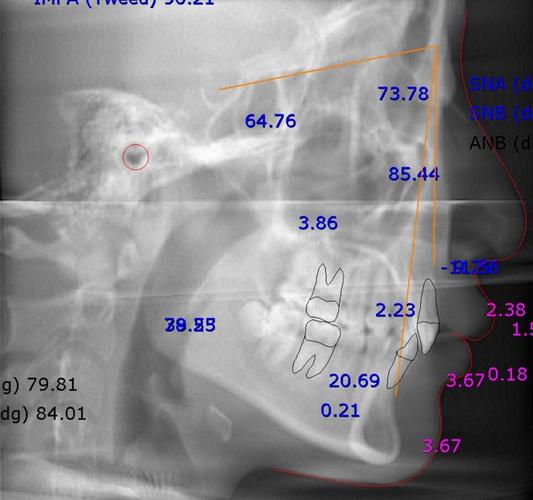

头颅侧位片的解读需通过标志点与测量线实现,以下为核心指标及临床意义(常用正常值范围参考中国汉族人群数据):

(一)骨骼测量指标

| SNA角 | 蝶鞍中心(S)-鼻根点(N)-上牙槽座点(A)的夹角 | 82°±4° | 反映上颌骨相对于颅骨的前后位置:>86°提示上颌前突,<78°提示上颌后缩。 |

| SNB角 | 蝶鞍中心(S)-鼻根点(N)-下牙槽座点(B)的夹角 | 80°±4° | 反映下颌骨相对于颅骨的前后位置:>84°提示下颌前突,<76°提示下颌后缩。 |

| ANB角 | SNA角与SNB角的差值(SNA-SNB) | 2°±2° | 上下颌骨的矢状关系:>4°提示上颌前突或下颌后缩,<0°提示下颌前突或上颌后缩。 |

| MP-FH角 | 下颌平面(MP,通过颏下点与下颌角点的连线)-颅底平面(FH)的夹角 | 32°±3° | 面部垂直高度:>37°提示长面型(下颌平面陡峭),<27°提示短面型(下颌平面平缓)。 |

| Y轴角 | 颏顶点(Y)-蝶鞍中心(S)的连线与FH平面的夹角 | 66°±3° | 下颌综合位置:>70°提示下颌位置靠前,<62°提示下颌位置靠后。 |

(二)牙齿测量指标

| U1-NA距 | 上中切牙切端至NA连线的垂直距离 | 4mm±2mm | 上切牙突度:>6mm提示上切牙前突(深覆盖常见),<2mm提示上切牙舌倾。 |

| U1-NA角 | 上中切牙长轴与NA连线的夹角 | 22°±5° | 上切牙倾斜度:>28°提示上切牙唇倾,<16°提示上切牙舌倾。 |

| L1-NB距 | 下中切牙切端至NB连线的垂直距离 | 2mm±2mm | 下切牙突度:>4mm提示下切牙前突(反颌或深覆盖常见),<0mm提示下切牙舌倾。 |

| L1-NB角 | 下中切牙长轴与NB连线的夹角 | 30°±6° | 下切牙倾斜度:>37°提示下切牙唇倾,<23°提示下切牙舌倾。 |

| IMPA角 | 下中切牙长轴与下颌平面(MP)的夹角 | 95°±6° | 下切牙倾斜度:>102°提示下切牙唇倾(易导致下前牙拥挤),<88°提示下切牙舌倾。 |